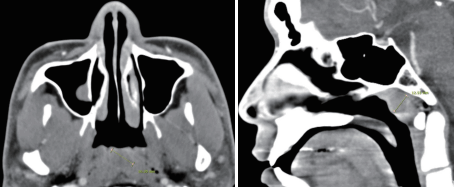

위 병변에 대해 조영증강 CT 검사를 시행하였으며, 조영 증강되지 않는 12×16 mm의 낭성 종괴가 비인강 상부에 확인되었다.

감별해야 할 질환으로는 수막류 또는 뇌수막류가 있으며 CT 또는 MRI를 통해 두개 내와 교통이 있는지 확인해야 한다.